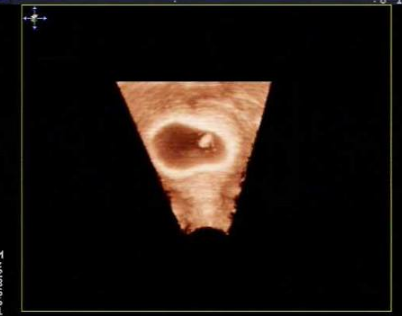

雙角子宮圖片

雙角子宮 (7)

雙角子宮 (8)

雙角子宮 (9)

雙角子宮 (55)

雙角子宮 (56)

雙角子宮 (57)

雙角子宮 (58)

雙角子宮 (59)

雙角子宮 (6)

雙角子宮 (60)

雙角子宮 (61)

雙角子宮 (48)

雙角子宮 (49)

雙角子宮 (5)

雙角子宮 (50)

雙角子宮 (51)

雙角子宮 (52)

雙角子宮 (53)

雙角子宮 (54)

雙角子宮 (44)